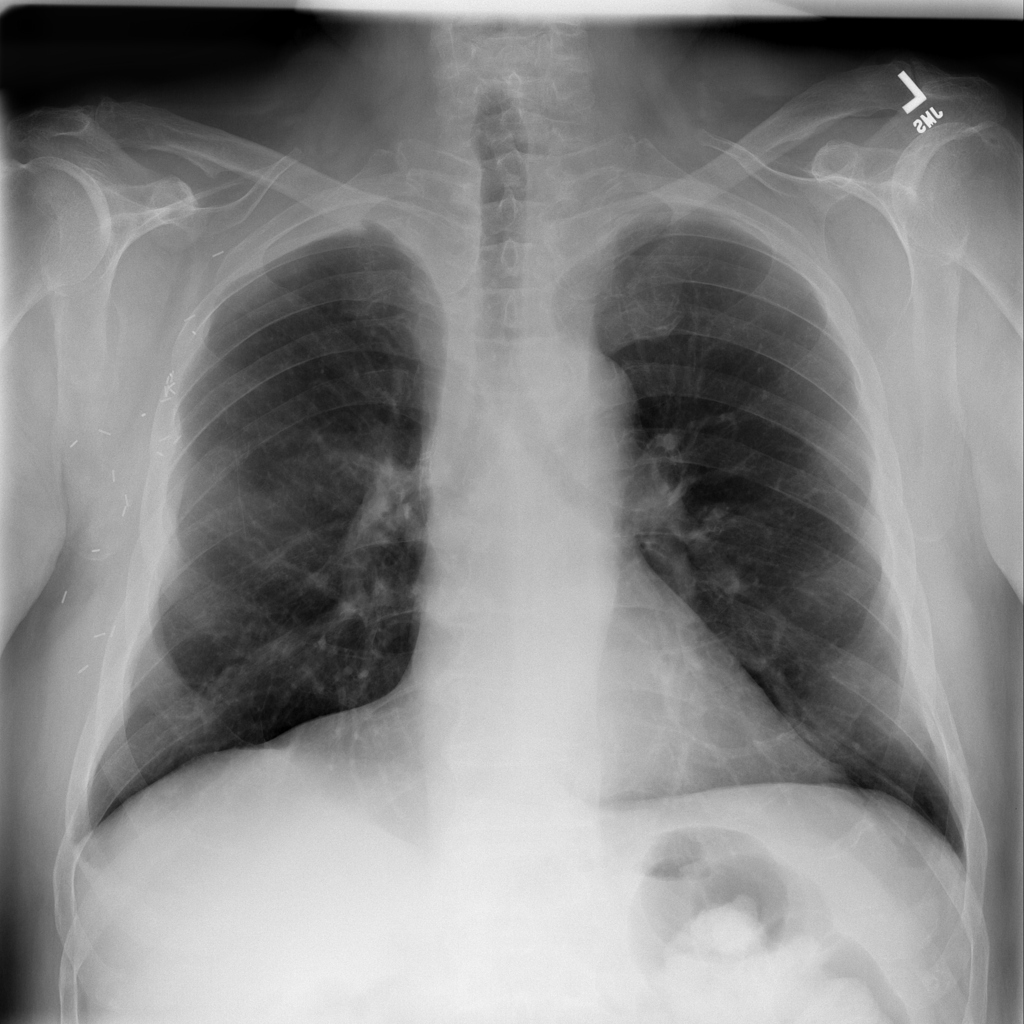

Pneumonia

Pneumonia is an infection of the lung tissue, often caused by bacteria, viruses, or less commonly fungi. On chest X-ray it can appear as focal or patchy air-space opacity, though imaging alone does not always prove the cause.

Showing up to 90 reference images for Pneumonia.

PAT-C0E5 · IMG-015Pneumonia

PAT-C0E5 · IMG-015

AP